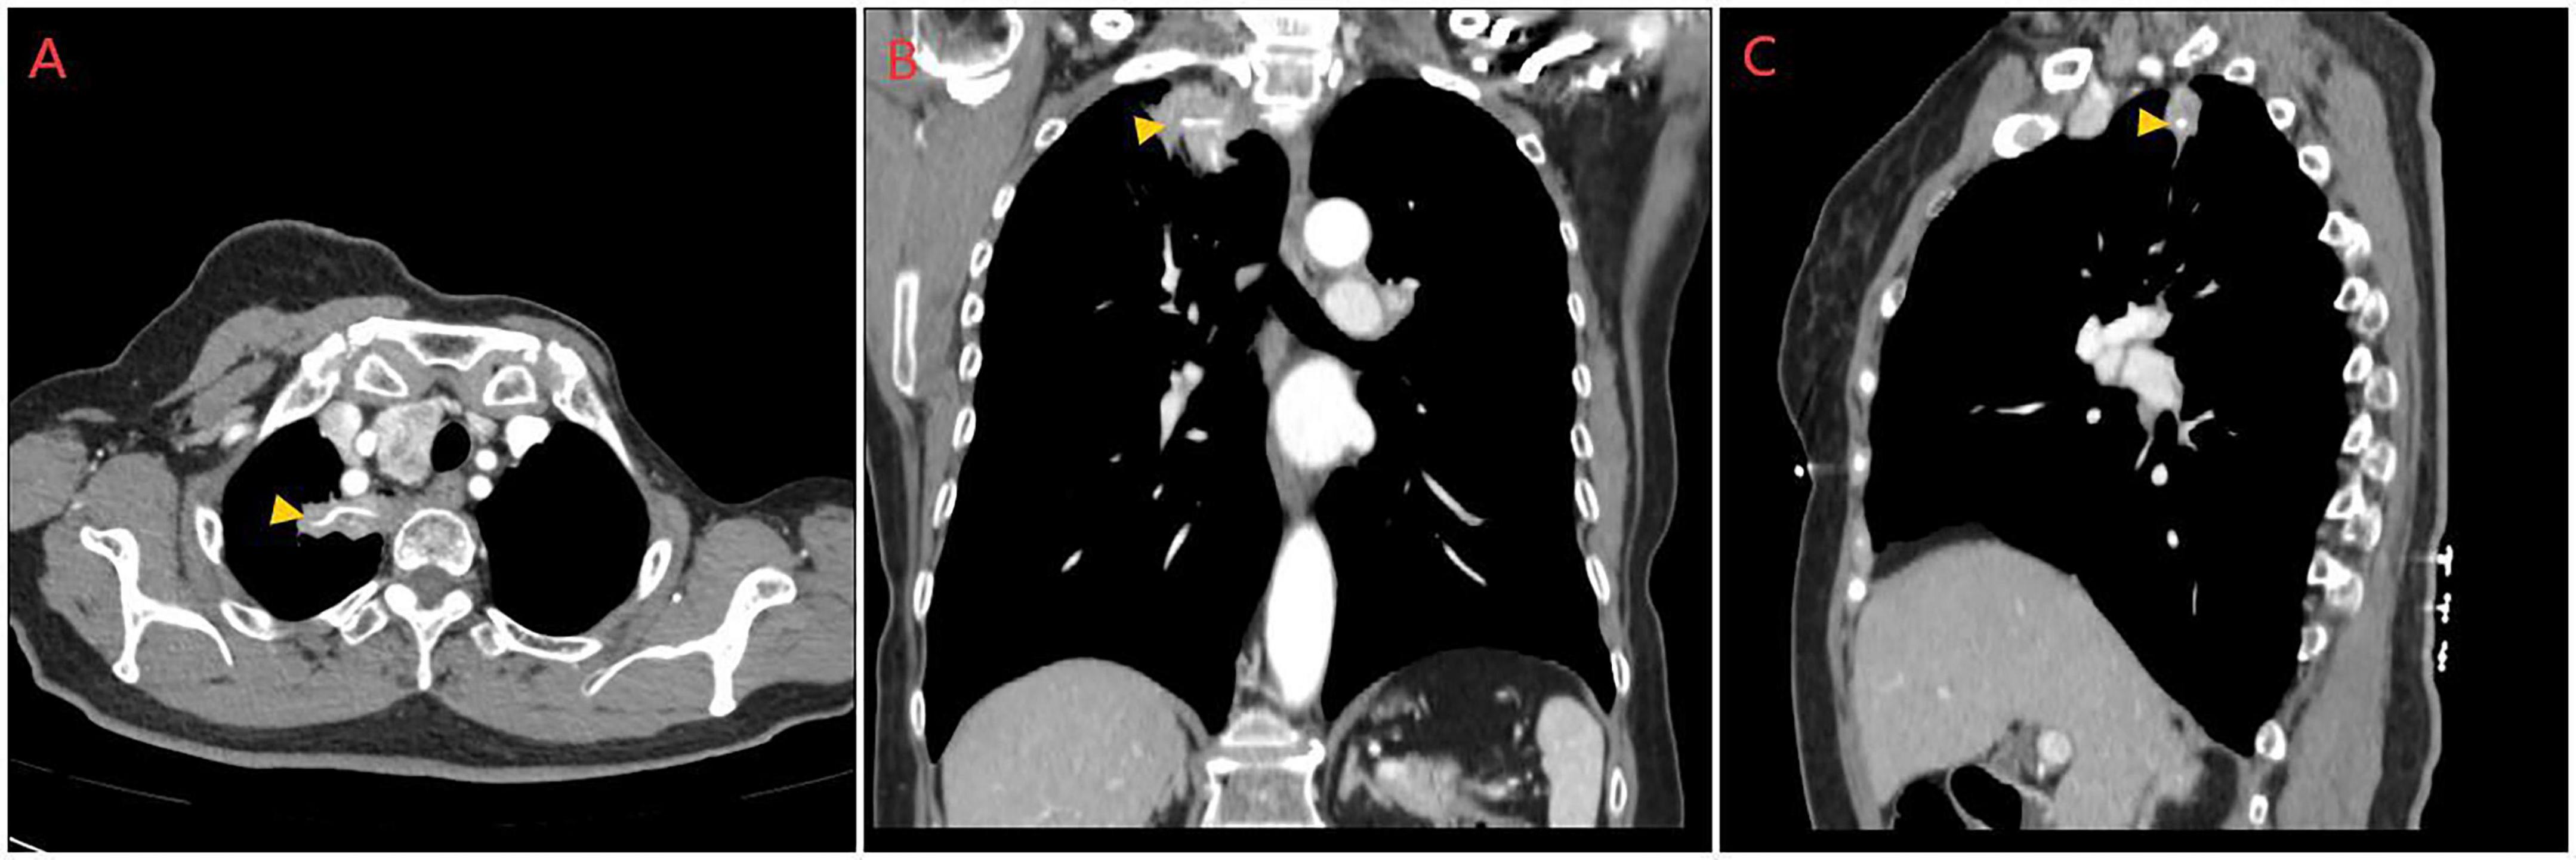

The patient was directly admitted to the hospital on this same day. Upon hospital admission, pulse, blood pressure, and temperature were normal. The physical examination revealed a barrel chest, diminished respiratory effort, reduced breath sounds, and the presence of wet rales and rhonchi in both lungs. Lab results were within normal parameters except for glycated hemoglobin was 6.7% and uric acid was 383 μmol/L. A repeat contrast-enhanced chest CT still showed the same result (Figure 1), but pneumonia or pulmonary tuberculosis could not be excluded. Tuberculosis of the lungs most commonly occurs in the posterior tip of the upper lobe or the dorsal segment of the lower lobe. Given the history of fish bone impaction, a migrated foreign body was suspected. Upon completion of preoperative investigations, Endoscopic retrieval was not feasible considering that the foreign body is located in the pulmonary parenchyma and surrounded by an inflammatory pseudotumour. On the October 18th 2024, under general anesthesia, a thoracoscopic wedge resection of the right upper lung lobe was performed, with a total operative duration of 110 min. The postoperative isolated specimen confirmed the presence of a 3 cm fish bone embedded in the lung tissue (Figure 2). And the pathological examination revealed lung tissue exhibiting suppurative inflammation and abscess formation (Figure 3). The suppurative inflammation and abscess formation surrounding the fish bone indicated high risk of progressive infection. Without prompt intervention, potential complications included: (1) Abscess expansion leading to pulmonary necrosis or bronchopleural fistula; (2) Hematogenous dissemination causing sepsis, particularly dangerous in this diabetic patient (HbA1c 6.7%); (3) Erosion into pulmonary vessels exacerbating hemoptysis. The embedded location adjacent to the mediastinum further raised concern for mediastinitis, which carries >20% mortality in delayed presentations. Thoracoscopic resection was thus prognostically critical to prevent life-threatening sequelae. The patient experienced a smooth recovery following the surgery and was discharged 2 days later. Tolerability was assessed through: Daily pain scores (NRS consistently ≤ 3/10 with non-opioid analgesia); Documentation of ambulation/spirometer compliance; Normoglycemia maintained via dietary controlling. No treatment-related adverse events occurred. At the 1-month follow-up, she remained asymptomatic. A confirmatory chest radiograph revealed no abnormality. The patient’s delayed presentation (20 days after hemoptysis onset) may including potential factors: (1) No abnormalities were found in laryngoscopy at the first visit and no discomfort symptoms for a long time before the onset of hemoptysis; (2) Cultural perception – attributing symptoms to “heatiness” or age-related decline rather than foreign body complications. These factors underscore challenges in timely diagnosis of occult foreign body migrations in resource-limited populations.

FIGURE 1

CT scan images in three views: axial (A), coronal (B), and sagittal (C). Each image highlights a specific area within the thoracic region using a yellow arrowhead. The scans reveal structures and tissues, displayed in varying shades of black and white, indicating different densities.

Figure 1. Preoperative contrast-enhanced chest CT images. (A) Transverse plane, (B) Sagittal plane, and (C) Coronal plane views demonstrating a linear, high-attenuation foreign body (fish bone, indicated by orange arrows) embedded within the right upper lobe. The foreign body is surrounded by a focal area of consolidation and ground-glass opacity, consistent with an inflammatory pseudotumor. The multi-planar reconstruction clearly illustrates the intraparenchymal location of the fish bone and its relation to the surrounding lung architecture.